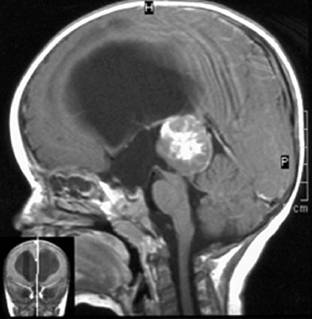

Эпендимома головного мозга

Эпендимома головного мозга. Опухоль из эпендимальной ткани желудочковой системы головного мозга. Клинически проявляется, прежде всего, признаками повышенного внутричерепного давления, а также атаксией, нарушениями со стороны зрения и слуха, судорожными приступами, нарушением речи и глотания. Диагностика осуществляется преимущественно при помощи МРТ головного мозга, спинальной пункции, ЭЭГ, гистологического исследования. Основу лечения составляет радикальное удаление эпендимомы с последующей лучевой или химиотерапией. У взрослых применяется стереотаксическая радиохирургия.

Эпендимома головного мозга - опухоль ЦНС, берущая свое начало из эпендимоцитов. Последние представляют собой эпителиоподобные клетки, образующие эпендиму - тонкую эпителиальную выстилку церебральных желудочков и центрального спинномозгового канала. Эпендимомы составляют до 8% всех опухолей головного мозга, относятся к глиомам. Эпендимомы чаще встречаются в детском возрасте, около 60% больных составляют дети первых пяти лет жизни. По своей распространенности эпендимома головного мозга занимает 3-е место среди всех церебральных опухолей у детей. В детском возрасте более часто, чем у взрослых, наблюдаются ее злокачественные варианты.

Эпендимома головного мозга чаще образуется в задней черепной ямке. Во многих случаях характеризуется медленным ростом, отсутствием прорастания в окружающие церебральные ткани. Однако по мере роста новообразования оно может вызвать масс-эффект - сдавление головного мозга. Метастазирование эпендимомы происходит преимущественно по ликворным путям и, как правило, не выходит за пределы ЦНС. Наиболее часто отмечаются ретроградные метастазы в спинной мозг. Лечение эпендимом является актуальной проблематикой современной онкологии, неврологии и нейрохирургии.

Выраженный ликворно-гипертензионный синдром, появление другой неврологической симптоматики или впервые возникший эпиприступ являются для невролога поводом к направлению пациента на МРТ или КТ головного мозга. МРТ головного мозга предпочтительнее, поскольку дает более полную информацию и позволяет избежать лучевой нагрузки, особенно, когда речь идет об обследовании ребенка. Для детей до года этапом первичной диагностики может стать нейросонография, которая выполняется через еще незакрывшийся родничок.